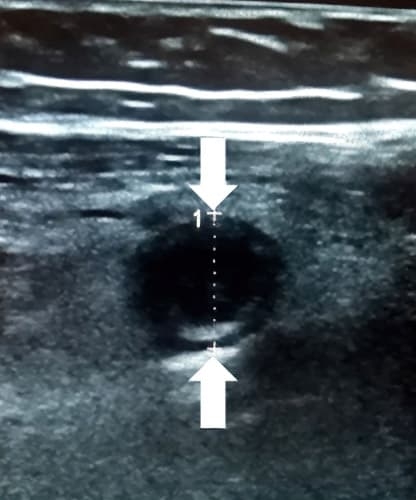

При поперечном сканировании напоминает «мишень»: внутреннее гиперэхогенное кольцо отображает воспаленный и отечный подслизистый слой; наружное гипоэхогенное (или анэхогенное) кольцо отображает воспаленный и отечный мышечный слой (см. рис. 2, 2а).

Рисунки 2, 2а. При поперечном сканировании аппендикс имеет вид «мишени».